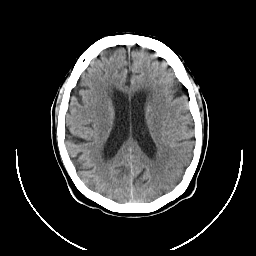

CT Study #1 -- Slice #17

Tour 1: Next/Previous/Start: The initial CT is shown here. It was obtained several hours after the onset of symptoms and was interpreted as normal.

[Home][Help][Clinical][Tour 1] Slice 17